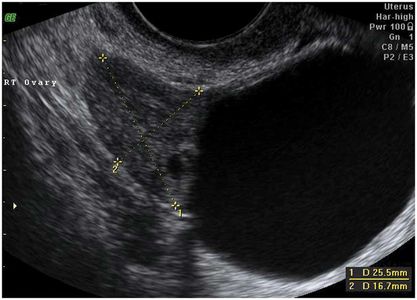

Is it an ovarian cyst? It could be hydrosalpinx, endometrioma, or paraovarian cyst.

Every pregnant woman should have an ovarian cyst. This cyst is the corpus luteum, the “cyst of pregnancy,” which produces the hormone Progesterone. All pregnancies are dependent upon progesterone for the first 10-12 weeks of gestation. When the corpus luteum is surgically removed before 11 weeks gestation, most pregnancies will end in miscarriage. Miscarriage can be prevented with progesterone supplementation until 12 weeks gestation.

Most corpus luteum measure less than 5 cm. Sometimes we discover ovarian cysts which are larger than 5 cm, and which persist past 12 weeks. Ovarian cysts in pregnancy can be categorized as follows:

The need to worry, or the medical indication to intervene (to remove the cyst with surgery) is based on the combination of size, description, gestational age and symptoms. One end of the spectrum is the Absolute Need to remove a 12 cm cyst that is clearly causing pain at 15 weeks of pregnancy. The other end of the spectrum is warning Against removing a 4 cm simple cyst that is not causing any pain. Most patients have something in between.

Ovarian cysts can lead to a number of potential problems. In pregnancy the problems are more acute in the asymptomatic phase because the risk of premature delivery caused by (or associated with) surgical intervention Increases with gestational age after approximately 20 weeks. Also, the window for laparoscopic surgical management of ovarian cysts closes as the pregnancy continues past 20 weeks.